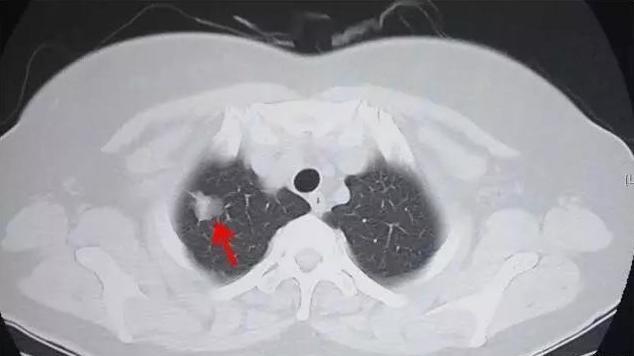

ct对你的必要性——早期肺癌两大高危人群,不是每个医生都会说

看图识病:ct图片(1)